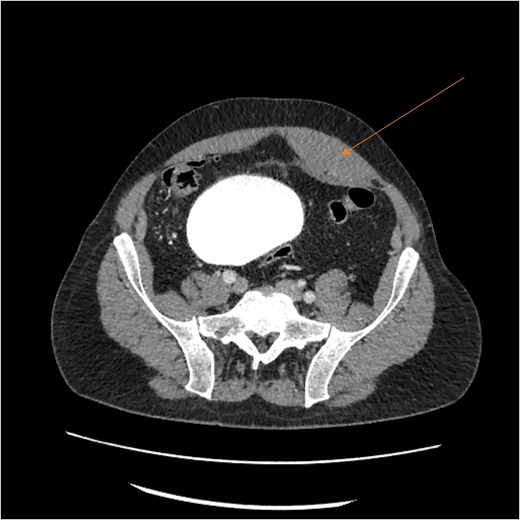

By hospital day 6, the patient’s condition improved. He was weaned from mechanical ventilation, his renal function improved (creatinine declined to 0.7 mg/dl), and hemoglobin stabilized at 8.4 gm/dl. The patient was clinically stable, and on hospital day 8, he was set up for discharge to a rehabilitation institution. However, on this day, he developed generalized abdominal pain associated with tachycardia, pulse = 118, and leukocytosis (white blood cells = 14.8 × 109/l). Physical exam revealed a distended abdomen with diffuse tenderness and sluggish intestinal sounds. A CT scan showed a large volume of pneumoperitoneum, minimal free fluid, and mildly dilated small bowel loops, consistent with a hollow viscus perforation with no identifiable source of perforation (Fig. 5) and a compression of rectosigmoid region against sacral promontory by the enlarged hematoma (Fig. 6). The right colon was decompressed compared with the prior study, and the RSH size remained unchanged, but there was progression of VTE burden. Prior to the acute deterioration, the patient had intermittently reported mild abdominal discomfort, which was initially attributed to the known RSH. There were no clinical signs suggestive of bowel obstruction, such as vomiting or significant abdominal distension. While the patient noted some degree of constipation, he reported that this was consistent with his baseline bowel habits and did not raise concern for new pathology.

CT scan demonstrating pneumo-peritoneum (arrow), indicative of a hollow viscus perforation.

CT scan demonstrating compression of large bowel (arrows) by the enlarged hematoma.